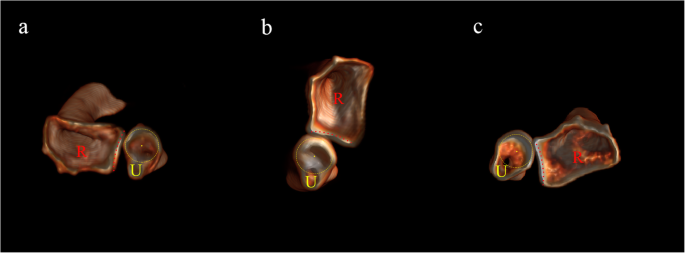

Preoperative MRI images of the right forearm (MRI Sequence: PD_TSE_SPAIR). a: Coronal image shows bone contusion of the capitellum of the humerus and proximal ulna (White arrow), as well as partial rupture of the medial collateral ligament (Yellow arrow). b: Sagittal image shows high signal around the proximal IOM (Red arrow). c: Axial image shows rupture of the proximal IOM from the dorsal attachment (Red arrow). R: Radius; U: Ulna

Radiographs of both forearms were taken for comparison, revealing volar dislocation of the radial head and dorsal dislocation of the distal radius without associated fracture on the injured side, which formed a criss-cross appearance on the lateral radiograph (Fig. 1). Computed Tomography (CT) scan was also applied to rule out associated fractures. To further evaluate the soft tissue injuries, Magnetic Resonance Imaging (MRI) of the forearm was taken, revealing partial rupture of the proximal IOM from its dorsal attachment and no impairment of the middle portion of the IOM, as well as partial rupture of the medial collateral ligament (MCL) (Fig. 2). Aside from ligamentous injuries, bone contusion was also detected on the capitellum of the humerus and the proximal ulna on MRI images.